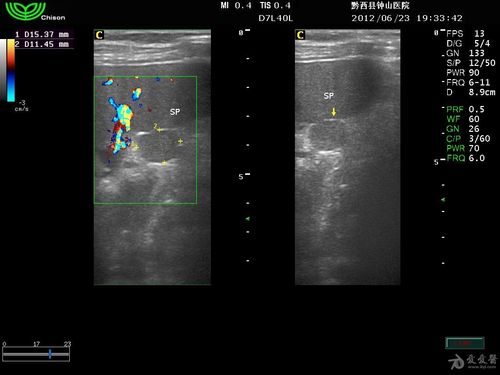

请看看这是副脾吗 - 超声医学讨论版 - 爱爱医医学论坛 - 爱爱医医学

副脾超声图片

副脾彩超图片